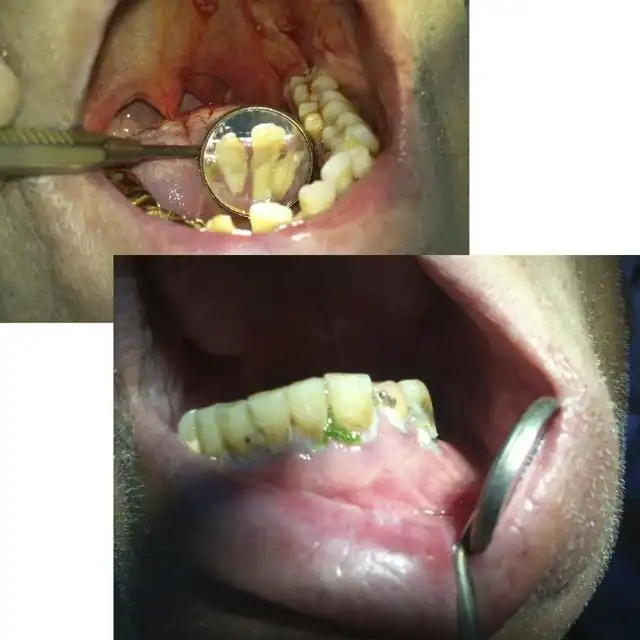

Угадайте, а сколько лет этому пациенту? По понятным причинам я не фотографировал его лицо полностью… Изначально он обращался около двух месяцев назад с переломом нижней челюсти в области суставного отростка слева, и шины наложить ему не могли, т.к. зубов целых почти нет… Был направлен в областную больницу, где походил с пращевидной бинтовой повязкой, и был отпущен домой… Остеосинтеза никто ему не делал. А потом спустя месяца два попал ко мне, после того как у себя на работе упал и ударился тем же местом)))) Очень «правдоподобно»… Но не в этом суть, парню 25 лет!!! Считает, что зубы разрушены, т.к. он на вредном производстве на заводе работает. Но гораздо более вероятная причина — нежелание чистить зубы. На фотографии видно, сколько там налета. И так многие выдумывают самые невероятные причины: работа с кислотой, жизнь в тайге, дальние плаванья, утрата зубов за один месяц после родов и т.п. Все это может повлиять в какой-то степени, но на деле у всех этих пациентов ужасная гигиена и последнее посещение стоматолога при царе Грохе. А у нашего парня зато татуха на всю правую руку, и на то, чтоб ее сделать, он нашел и время, и деньги, и желание… Это наш менталитет… Ездить на дорогой машине, понаделать татух, пирсинг, ходить в дорогих шмотках, но при этом с грязными ушами и нечищеными зубами. Редко кто на приеме попадается с таким уровнем гигиены, чтоб можно было стоматологическое вмешательство проводить. Да-да, есть индекс гигиены специальный, и если он выше определенной величины, то удалять нельзя. Но на деле удаляю, т.к. если строго подходить, то принять можно будет 2-3 человек за смену, остальных отправлять чистить зубы… Но потом люди приходят и с удивлением спрашивают, почему лунка после удаления болит? Никому даже в голову не приходит, что одной из вероятных причин может быть помойка во рту… Так что, друзья, идете к стоматологу — почистите зубы хорошенько ( да и вообще их чистить надо)), даже этой мелочью вы обеспечите себе хорошее отношение врача, потому что чистый рот — большая редкость и приятная неожиданность для стоматолога( к сожалению).

А это его панорамная рентгенограмма. То, что обвел красным, надо удалять. В 25 лет этому парню надо ставить съемные пластиночные протезы. Это такие, как вы видели у своих бабушек и дедушек в стаканах на тумбочке у кровати…

Еще пару слов о гигиене… Вот два типичных пациента. У одного укроп на зубах, у второго камни (видны в зеркале). И это не самые яркие примеры. Представьте, что после удаления попадает в кровоточащую лунку… Меня вообще трудно удивить или вызвать отвращение, но некоторым удается. Иногда просто отправляю из кресла идти чистить зубы. Где? Меня не касается… Так обижаются!!! Тонкие натуры) Был случай, как одного такого запущенного принял, удалил зуб, но предупредил, что если еще раз с таким ртом придет, то я его не приму. Он пришел- картина та же. я ему в приеме отказал. Это первая смена была. А вечером зашел в кабинет зачем-то, там мой коллега прием вел, смотрю -сидит у него в кресле мой утренний пациент. Спрашиваю доктора, почистил ли тот мужик зубы, а он мне говорит, что такой помойки он не видел еще, как у него во рту… Занавес…